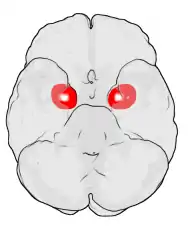

Frontal and side view of amygdala

Amygdala along with other subcortical regions, in glass brain.